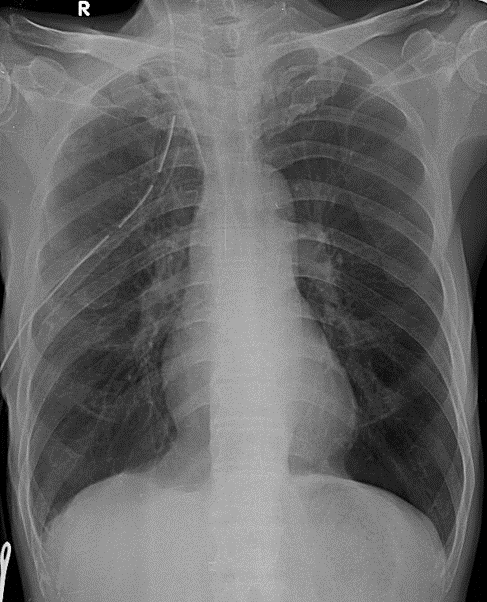

Hãy phân tích tình huống NAM 66 tuổi -CĐ: Hậu phẫu kém phí phổi (P), TKMP (P) nhiều lần, suy hô hấp

1-Ống dẩn lưu tràn khí màng phổi (P)